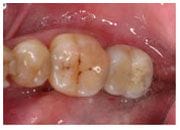

治療前